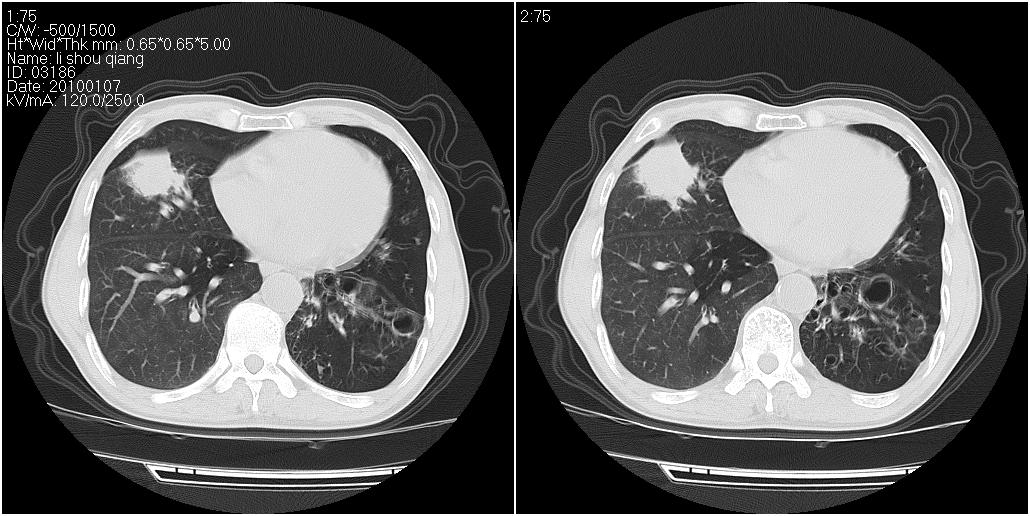

标题: CT24038:男性,58岁。主因咳嗽带血性CT检查。 [打印本页]

标题: CT24038:男性,58岁。主因咳嗽带血性CT检查。

右肺中叶外侧段见一不规则的软组织肿块,边缘可见毛刺,并见厚壁空洞,与胸膜分界欠清。另左下肺见多个小囊状扩张区

右肺中叶外侧段可见团块影,外形不规则,内见空泡征。左下肺见蜂窝状低密度透亮影,部分层面主动脉旁瘤样突出。考虑右肺中叶外围型肺癌可能性大,左下肺支气管扩张,主动脉弓瘤样突出。

1、右肺中叶周围型肺癌(内空泡)。

2、左肺下叶支扩,不除外合并肺囊肿。

3、建议冠状位重建除外主动脉弓息室样动脉瘤。